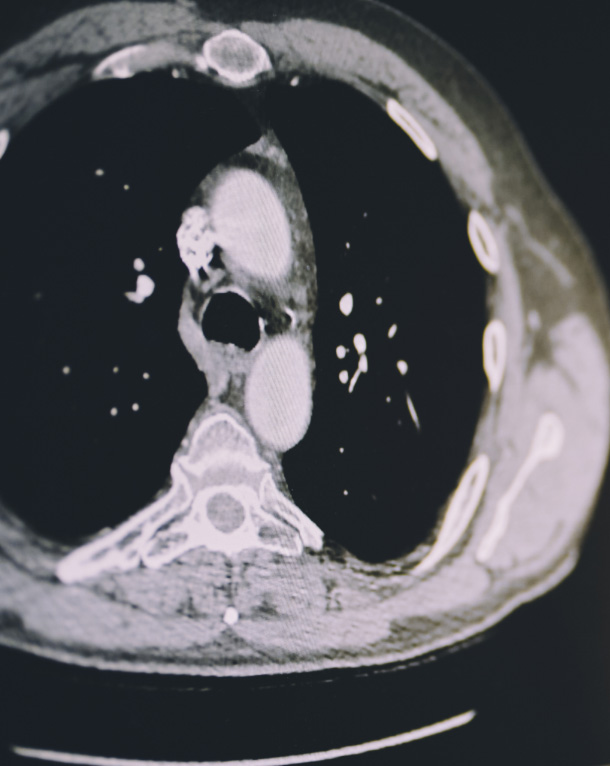

从科研到临床、转化并解锁医学图像数据。通过影研影像创新工场,探索人工智能(AI)、机器学习(ML)、数据挖掘和影像组学在临床研发战略中的真正潜力,将临床试验医学影像转化为深刻见解并开启新的可能性,包括早期癌症患者的精准识别。

借助人工智能医学影像分析技术重新定义患者病程,精准筛选目标患者、智能监测疾病复发、早期识别治疗无应答者,并解析患者特异性特征。